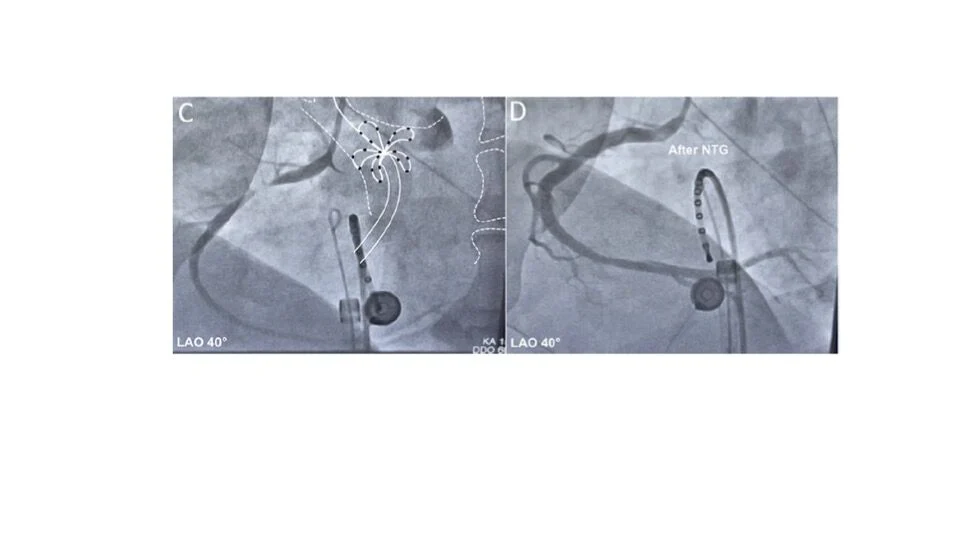

“Vasospasm and PFA – Overhyped or real problem?

Along with Prof. Guerra, I’ll be reviewing the latest insights on acute coronary spasm in Pulsed Field Ablation—from current evidence to practical mitigation strategies.